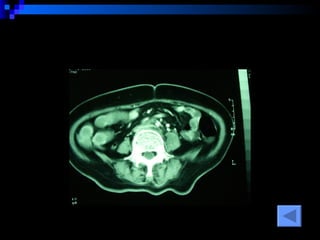

CT SCAN AAA juxtrareal -> bifurcation  Size 10*8*4 cm Inflamatory tissue  around AAA Intact renal artery Aortic dissection at juxtra renal -> bifurcation Bowel wall thickening at 3 rd -4 th  part of duodenum

CT SCAN AAAjuxtrareal -> bifurcation Size 10*8*4 cm Inflamatory tissue around AAA Intact renal artery Aortic dissection at juxtra renal -> bifurcation Bowel wall thickening at 3 rd -4 th part of duodenum